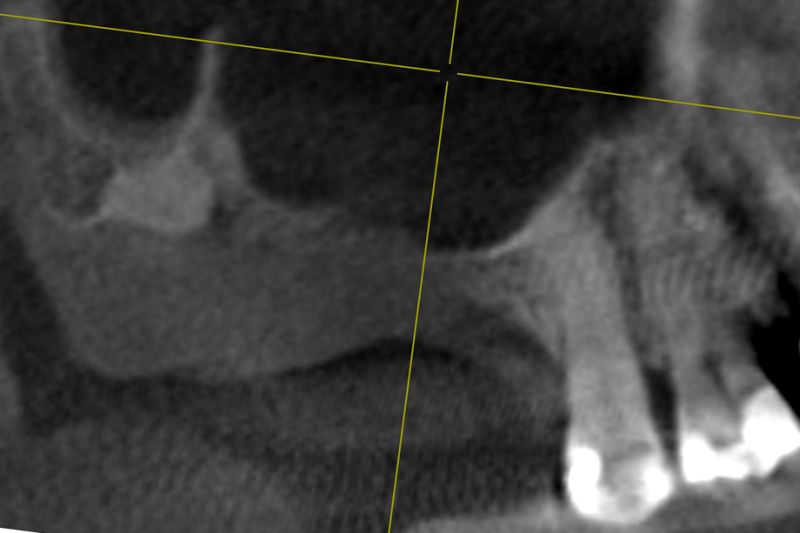

DVT image showing the reduced amount of bone available in the area of the mental foramen

DVT control after sinusitis surgery, residual bone height 1 mm